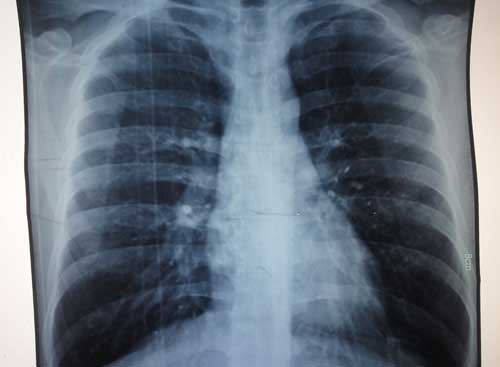

X线片示:双肩关节间隙狭窄,骨质受损,胸锁处有异常凸起。

(图:陈女士X线片显示胸锁部位有异常凸起,按压疼痛)